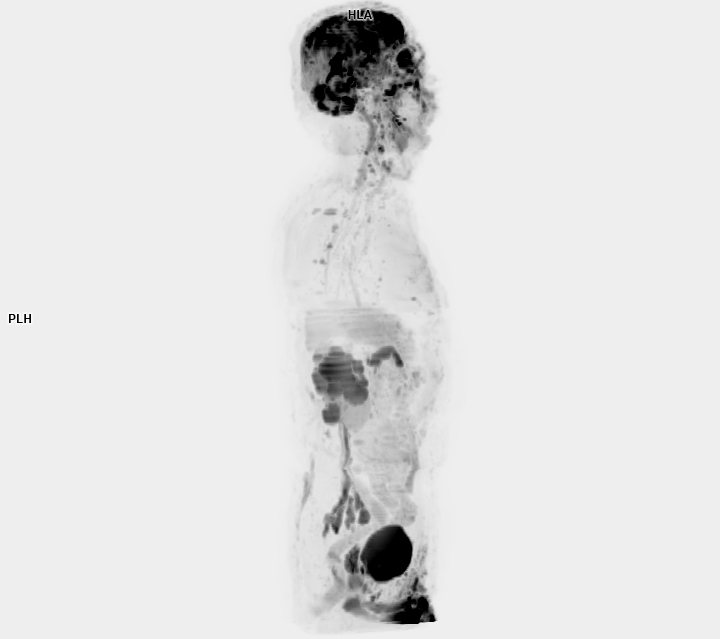

• 3 TESLA MR ÇEKİM GÖRÜNTÜLERİ

3 Tesla MR Çekim Görüntüleri

• 3 Tesla MR Çekim Görüntüleri